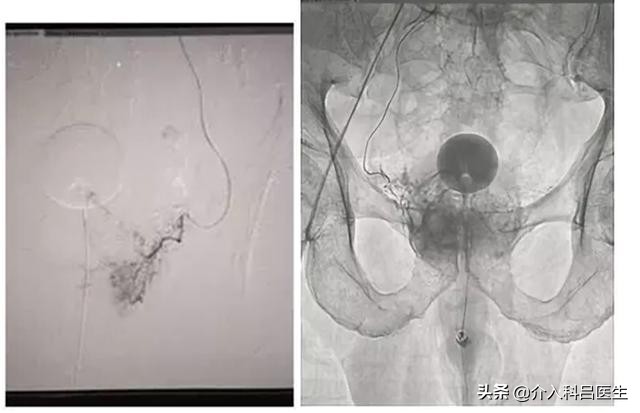

检查完后,我们就为王大爷安排了手术,由于患者年龄大、血管迂曲,前列腺动脉介入栓塞难度大,其主要体现在前列腺的供血血管非常纤细,周围组织比较多。

为了减少对周围组织的损害,使用微导管超选到前列腺动脉内进行栓塞。前列腺动脉的交通支比较丰富,前列腺动脉完全栓塞以后,前列腺还有直肠下动脉、会阴动脉和膀胱上动脉供血,因而不会产生坏死。微导管超选进入前列腺动脉,避开了周围组织,因而不会产生性功能障碍。